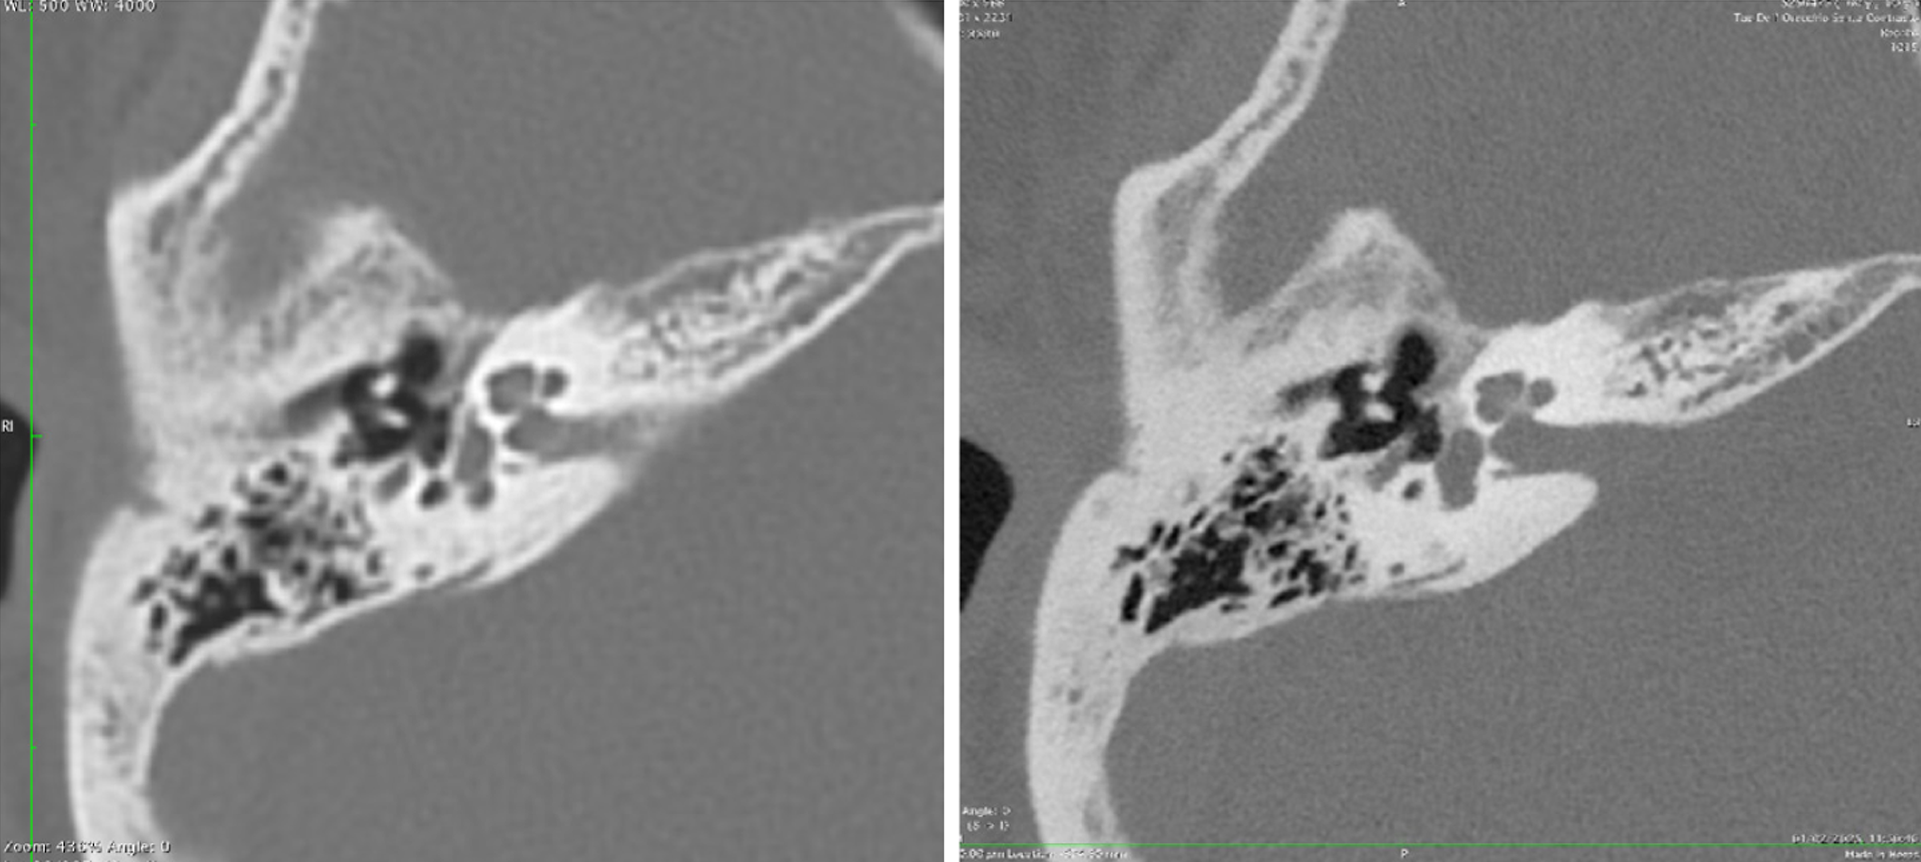

Figure 2 Cerebrospinal fluid-venous fistulas are challenging to detect using conventional computed tomography imaging.

NAEOTOM Alpha makes Cerebrospinal fluid-venous fistulas visible (orange coloured arrow). Copyright ©Siemens Healthineers AG 2024. The authors have obtained the permission (Supplementary material).